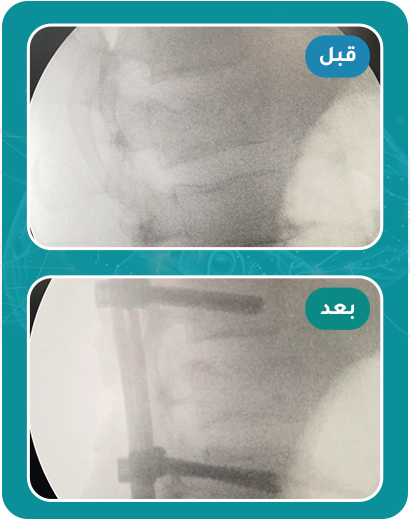

قصص مرضى تغيرت حياتهم للأفضل بعد العلاج